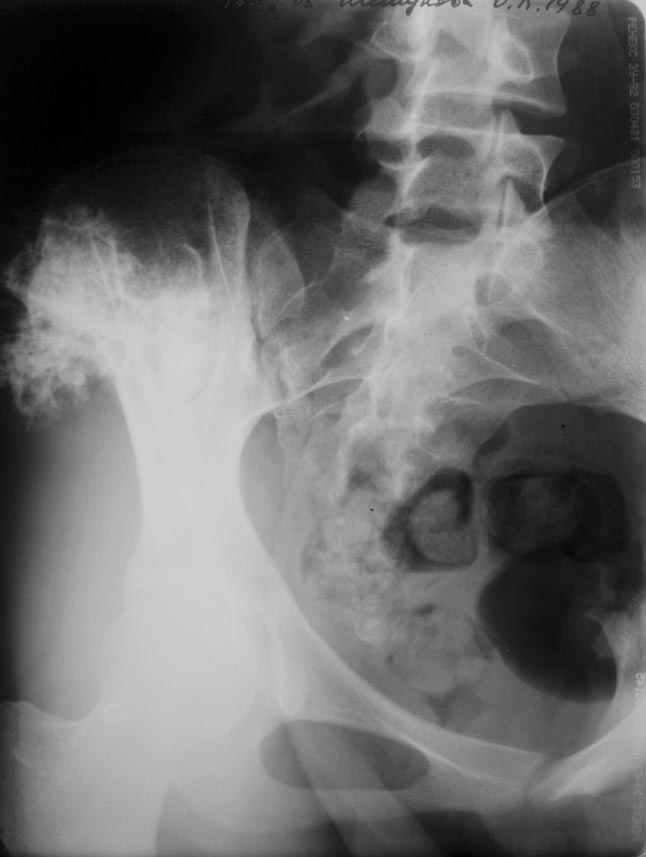

Получены результаты гистологического исследования.Процесс доброкачественный. Диагноз хондрома крыла таза подтвержден.Вопрос: чем и как закрыть предполагаемый значительный дефект крыла?

P.S. ещё фото

Отправитель: Пулатов Андрей Рифгатович 07 Июнь 2005, 17:00

Уважаемые коллеги, больную прооперировали. После выделения остеохондрома резецирована в пределах неизменённой кости. Выявлено, что гребень подвздошой кости не пострадал от опухоли. В результате резекции сформирован сквозной дефект в крыле подвздошной кости треугольной формы 6х7х8 см. В качестве трансплантата использована наружная кортикальная пластинка заднего отдела крыла подвздошной кости.

Трансплантат фиксирован на месте дефекта при помощи шурупов и проволоки. Кровопотеря 550 мл.

На фото этапы операции, R-gr.